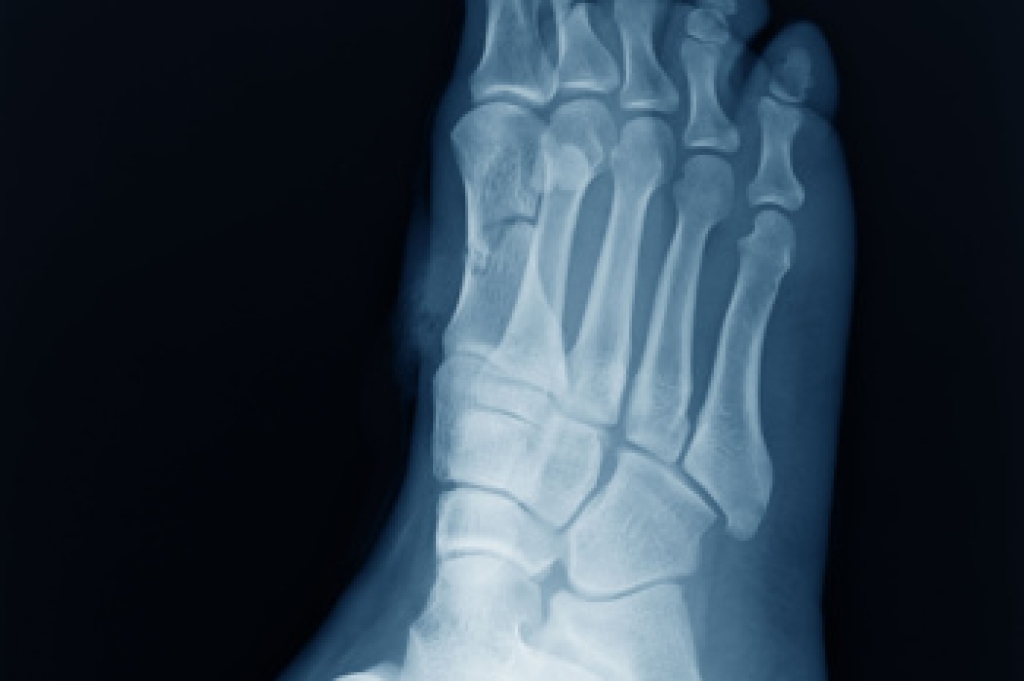

Osteoarthritis and rheumatoid arthritis both affect joints, but they develop in very different ways. Osteoarthritis is a wear-related condition that occurs when joint cartilage gradually breaks down over time. In the feet, it often causes stiffness, aching, and pain that worsens with activity and improves with rest. Rheumatoid arthritis is an autoimmune disease in which the immune system attacks joint lining. This leads to inflammation, swelling, warmth, and pain that may affect both feet symmetrically. Symptoms often feel worse in the morning or after periods of rest. Rheumatoid arthritis can also cause joint deformity if left untreated. Treatment approaches differ. Osteoarthritis care focuses on reducing stress on joints and improving movement, while rheumatoid arthritis requires medical management to control inflammation and protect joints. If foot pain, stiffness, or swelling persists, it is suggested that you see a podiatrist for an evaluation and treatment guidance.

Arthritis is a term that is commonly used to describe joint pain. The condition itself can occur to anyone of any age, race, or gender, and there are over 100 types of it. Nevertheless, arthritis is more commonly found in women compared to men, and it is also more prevalent in those who are overweight. The causes of arthritis vary depending on which type of arthritis you have. Osteoarthritis for example, is often caused by injury, while rheumatoid arthritis is caused by a misdirected immune system.

Arthritic symptoms range in severity, and they may come and go. Some symptoms stay the same for several years but could potentially get worse with time. Severe cases of arthritis can prevent its sufferers from performing daily activities and make walking difficult.